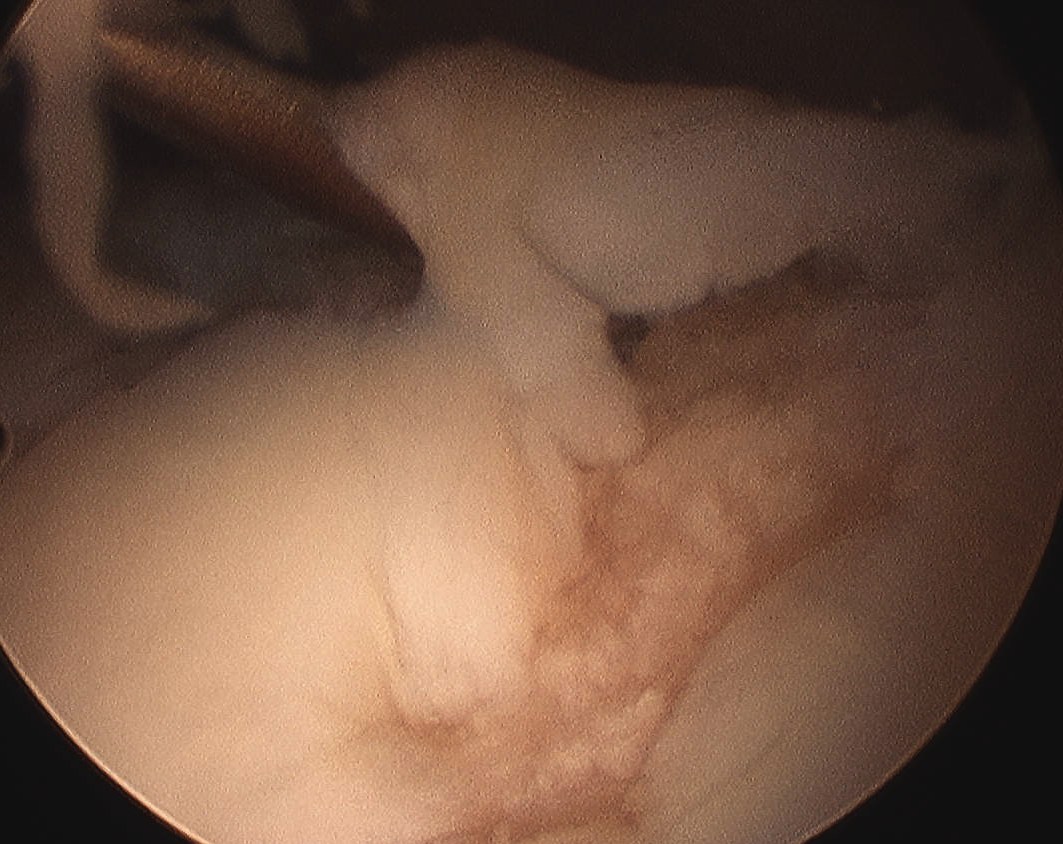

Arthroscopy

Patterns

Lateral facet - patella maltracking / trochlea dysplasia

Medial facet - patella dislocation and cartilage damage

Global - primary OA, patella fracture, obesity

Central trochlea - repetitive deep flexion

Medial facet OA Lateral facet OA